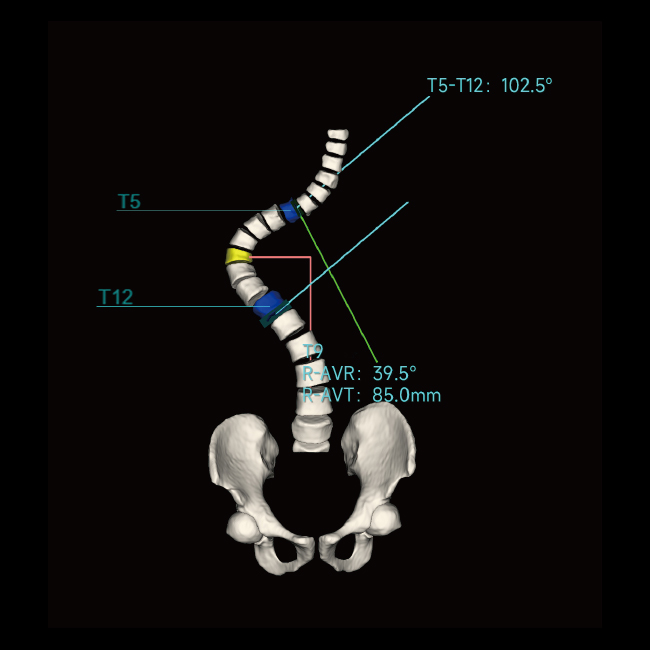

「 全 」全球首台三维骨关节与AI测量负重锥束CT

临床图像